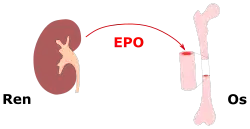

Since cytokine receptors play a role in haematopoiesis, cytokine receptors have also been a common topic to study in the treatment of hematopoietic disorders such as anemia. A major cytokine and cytokine receptor in the process of haematopoiesis is erythropoietin and the erythropoietin receptor. Both have important roles in activating and maintaining red blood cell production. Scientists have studied the uses of stimulating erythropoietin and the erythropoietin receptor for the production of red blood cells in diseases such as kidney disease or certain types of anemia.